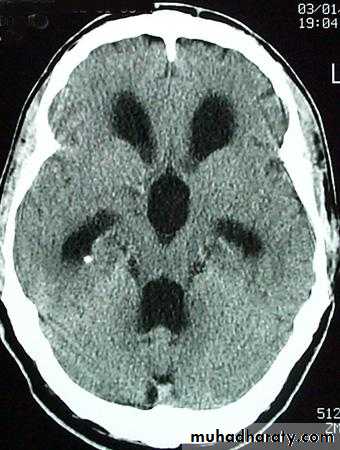

Medullo blastomaAge incidence between 5-15 Y represent about 35-40 %of PFT

Arise from the midline mainly within or from the roof of the 4 TH ventricle fill the fourth ventricle & seeding via the csf so can seen in the distal part of the spinal canal .

CT finding as well circumscribed lesion heterogeneous in density ,have solid & cystic part , with also scattered calcification little surrounded edema , the solid part is enhance

90 % present with obstructive hydrocephalous at the level of the 4Th V. with dilatation of the lateral V. ( body , frontal , temporal & third ventricle )